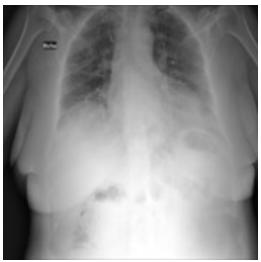

Second: the performance metrices for the proposed edge detection technique is measured for infected sample images using MATLAB and Zynq702 FPGA. The results of these performances are shown in Table 3.

Table 2 and Table 3 illustrate both the healthy and infected images, respectivly, the clarity of edges is observed. The tables indicate that using the proposed method with MATLAB led to a significant improvement in edge clarity in the Infected images compared to the healthy ones. This is due to the characteristics of the COVID-19 disease present in the infected images, which increase the complexity of the edges and make them less clear. They also indicate that the images produced by the proposed method are clearer than those from MATLAB, as the proposed method employs fixed-point arithmetic to represent numbers that are closer to edge values than the numbers used by MATLAB, which relies on floating-point arithmetic.

Table 3. Results for COVID-19 infected images

Input Image

MATLAB Result

FPGA Result